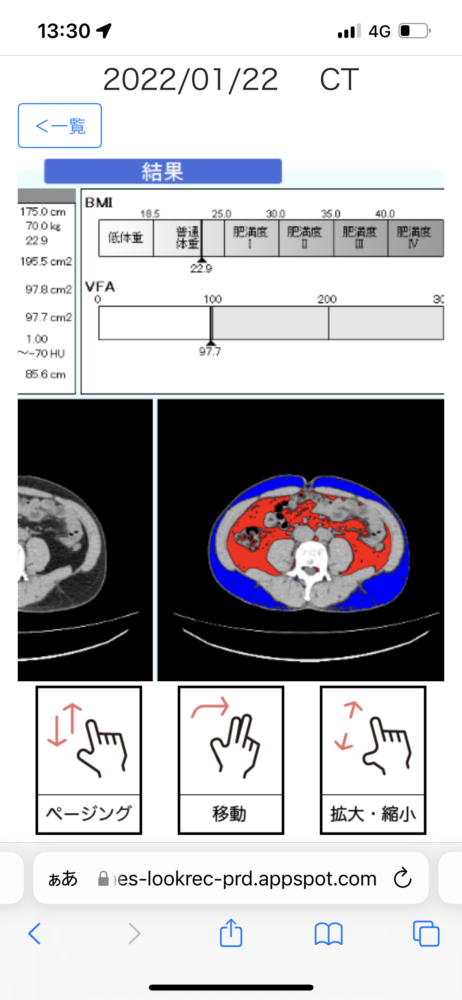

取材という名の雑談をしているうちに、脳のMRI画像や、身体のCTスキャン画像が送られてくる。速い! ちなみに、肥満ではなく、普通体重らしい。

これまで、医療従事者の方だけが持っていて、なぜか自分はゆっくり見ることができなかったこれらの画像を、自分のスマホで見ることができるのは新鮮な驚きだ。本来こうあるべきなのではないだろうか?